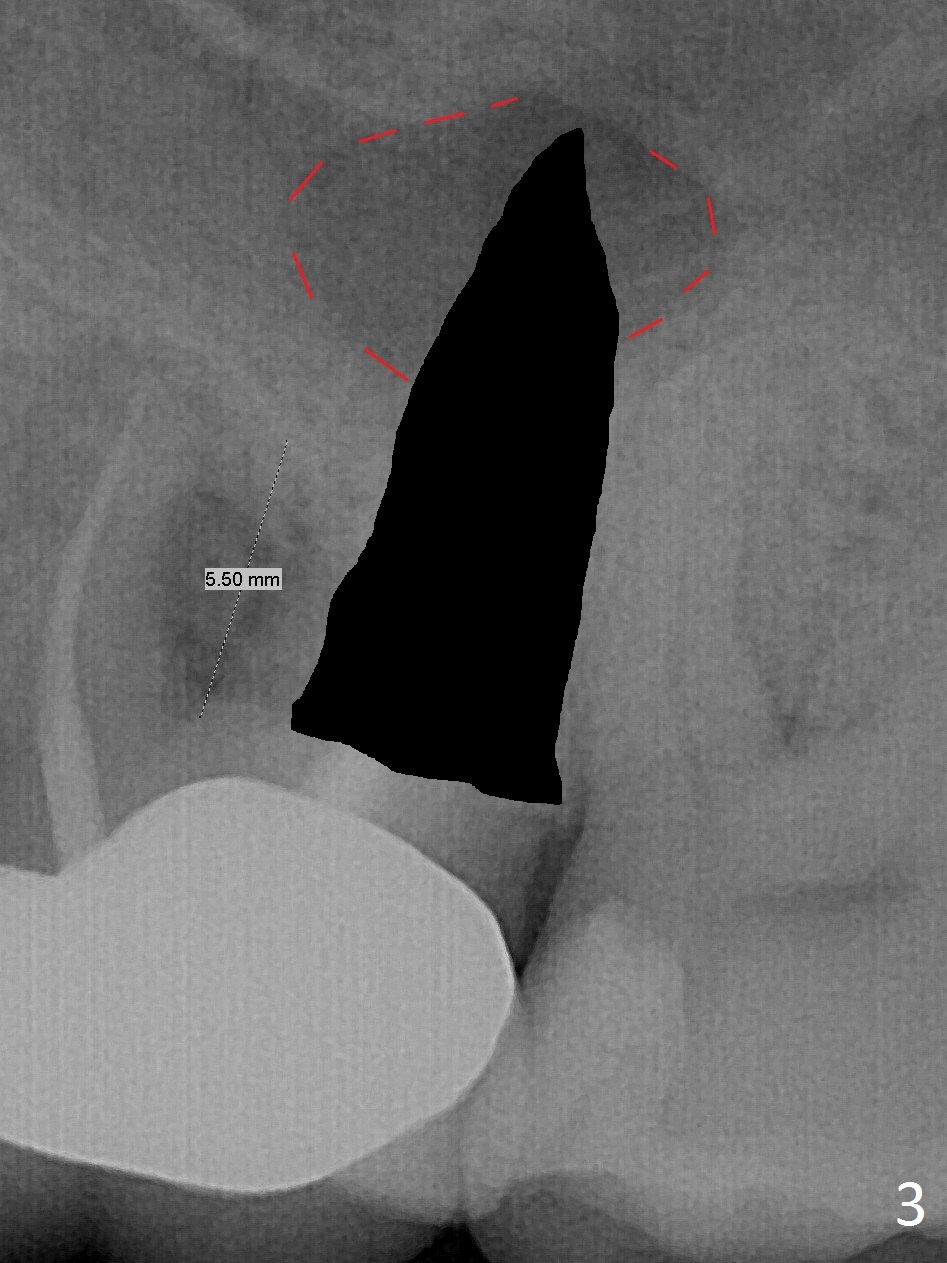

What is unclear preop is the large periapical radiolucency (Fig.1 red dashed line) of the palatal root (P) of the tooth #14.  When the tooth is extracted, it is difficult to remove granulation tissue from the palatal apical socket, which is enlarged (Fig.2 (impression of sockets),3).   The small dimension of the septum (~4x5 mm (Fig.1 pink) is also unrecognized preop, which leads to sinus perforation when 4.8 mm Magic Drill is used.  In spite of use of PRF plug and membrane, allograft does not stay in the osteotomy after placement of 4x11 mm dummy implant or 5 mm tap drill (Fig.4 for 9 mm).  Finally a 5.5x7 mm IBS implant is placed with 30 Ncm (Fig.5).  After placement of Osteogen plug in the apical portion of the sockets, allograft/Osteogen is placed in the remaining sockets (Fig. 5 *).  The latter is partially contained by a 6.5x4(3) mm abutment (A) and ultimately by an immediate provisional.